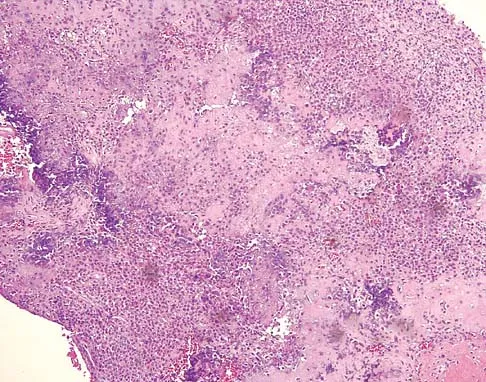

A 14-year-old boy reports pain in the distal thigh. He denies any history of trauma. Examination reveals tenderness and swelling of the distal thigh without effusion. A radiograph and CT scan are shown in Figures 10a and 10b. A biopsy specimen is shown in Figure 10c. Management should consist of

Explanation

Based on these findings, the patient has an aneurysmal bone cyst. Frequently, fluid-fluid levels can be detected on MRI or CT images. The histologic results show a lesion that consists of cavernous spaces filled with blood. The lining of the cavity contains spindle cells, multinucleated giant cells, and reactive bone. Curettage and bone grafting is the preferred treatment method. Without treatment, these lesions can become quite large and destructive. Radiation therapy is not recommended for resectable lesions. Chemotherapy is not required for these benign lesions. Simon MA, Springfield DS, et al: Common Benign Bone Tumors: Surgery for Bone and Soft Tissue Tumors. Philadelphia, PA, Lippincott Raven, 1998, pp 194-200.